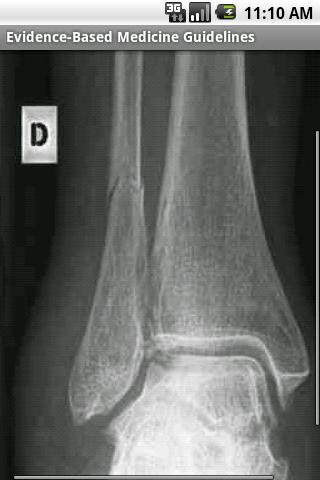

基于证据的医学指南(EBMG)具有近1,000个临床指南,包括诊断和治疗,以及支持每个建议的3,000多个证据摘要。 EBMG还包括1,000多个图像和直接传递到您的设备的广泛视频库。 EBMG经常更新。